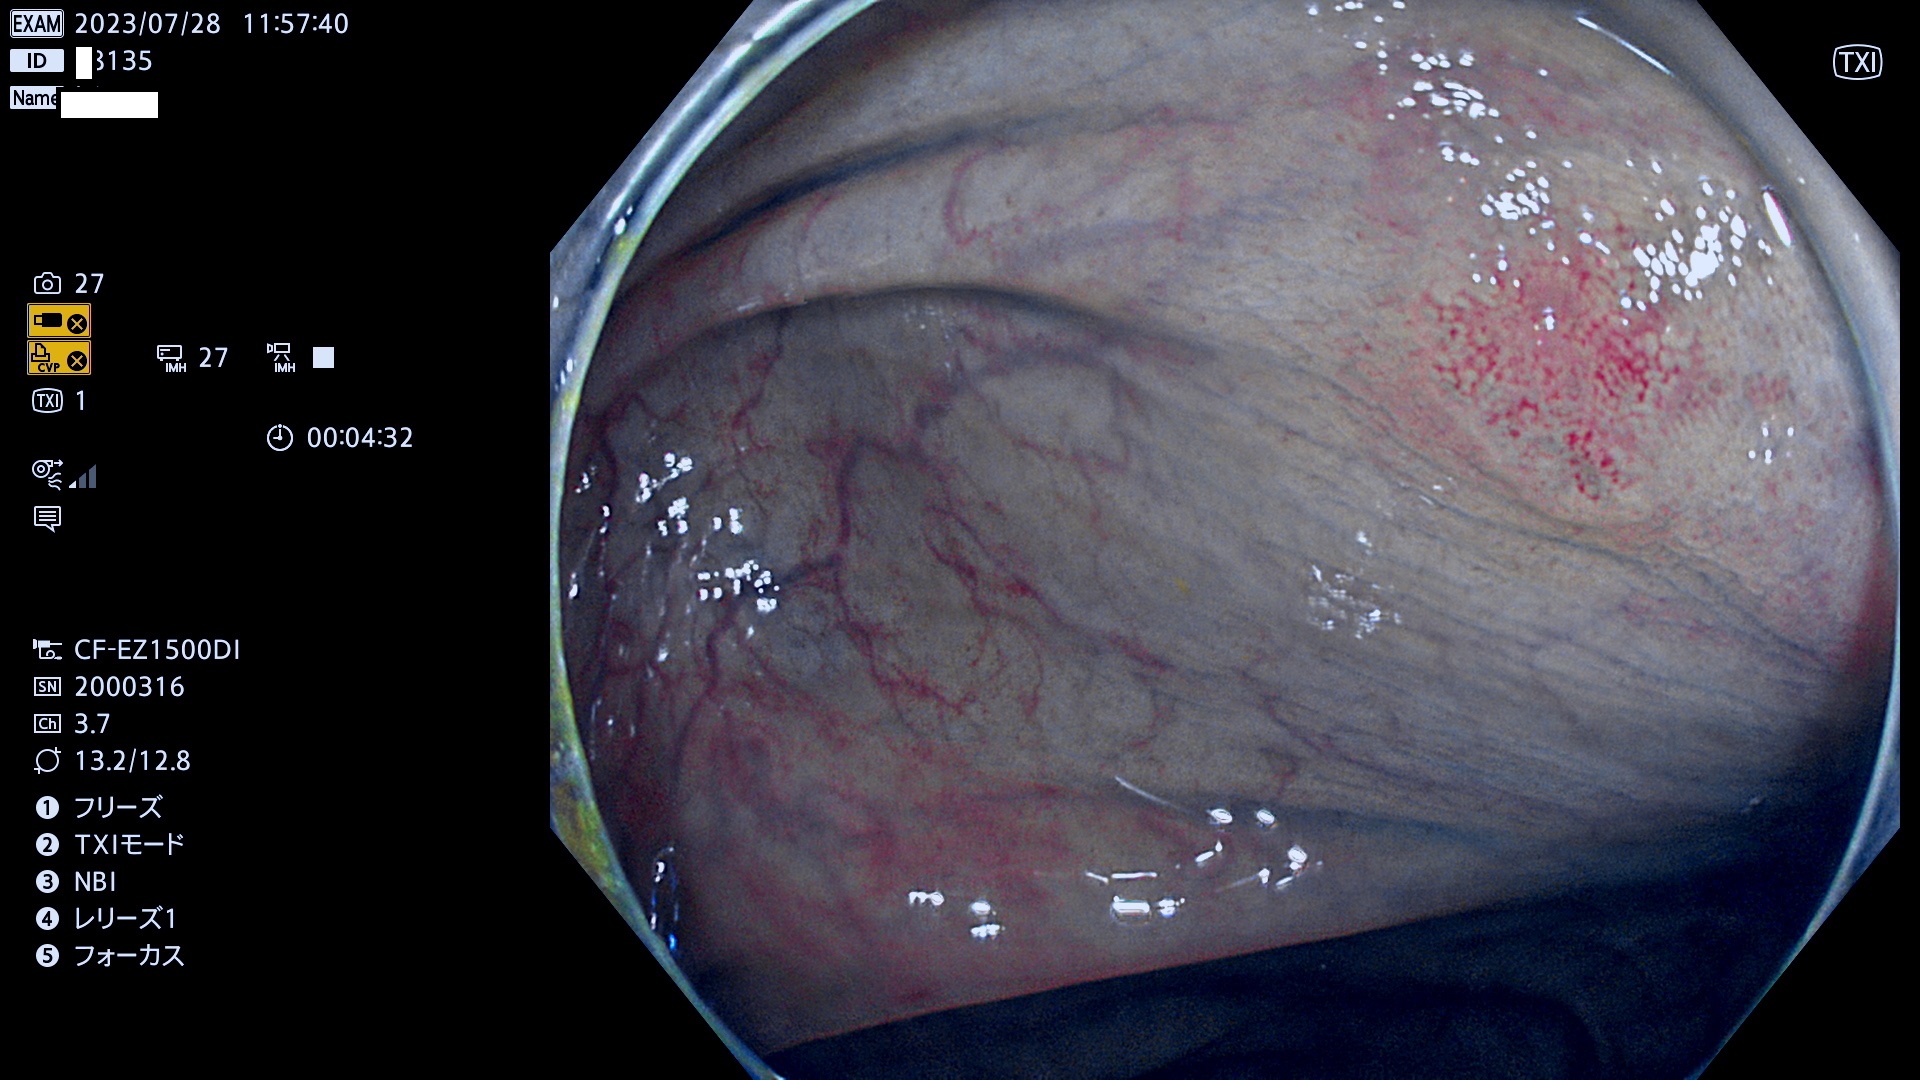

表面型腺腫(Flat Adenoma)の中で、完全に平坦な物をUb、陥凹している物をUcと呼びます。平坦隆起型(Ua)よりも、発見が難しく危険な病変です。このタイプは「内視鏡後・大腸癌の重要犯人」であり、この発見率は「腺腫発見率」よりも、重要な意味があります。

専門的)何故、陥凹していると危険? 癌遺伝子の変異が蓄積すると細胞分裂が盛んになり隆起するのでは?と通常は思われるでしょう。しかし実際は逆です。これは2022年の記事にある「細胞はストレスに直面したら細胞分裂を止める(細胞老化に入り休眠する)という生命の基本的現象」によるものです(Oncogene Stress)。細胞老化を起こすのが癌抑制遺伝子で、この安全装置(ブレーキ)が壊れると癌になります(休眠からの覚醒)。ですから陥凹は「まだ癌では無いが癌化の直前」を意味します。特に「小サイズなのに陥凹している」病変は短期間に腫瘍進化(⇒2021年記事)が起きたことを意味します(=ゲノム不安定性

専門的)Uc=De Novo癌? 内視鏡の解像度が低かった時代、このような説もありました。しかし今日の高精度内視鏡では良性の微小なUc型腺腫が日常的に見つかります。私見ですが「Ucこそが多段階発癌(Adenoma-Carcinoma Sequence)のMain Route」と考えます。

毎週の検査(木・金・土・日)に発見されたUb、Uc型・腺腫を、その週の日曜の夜にUPし1週間、提示します。

抽出の対象期間 2023年7月27日(木)〜7月30(日)の4日間(48件の検査)11件